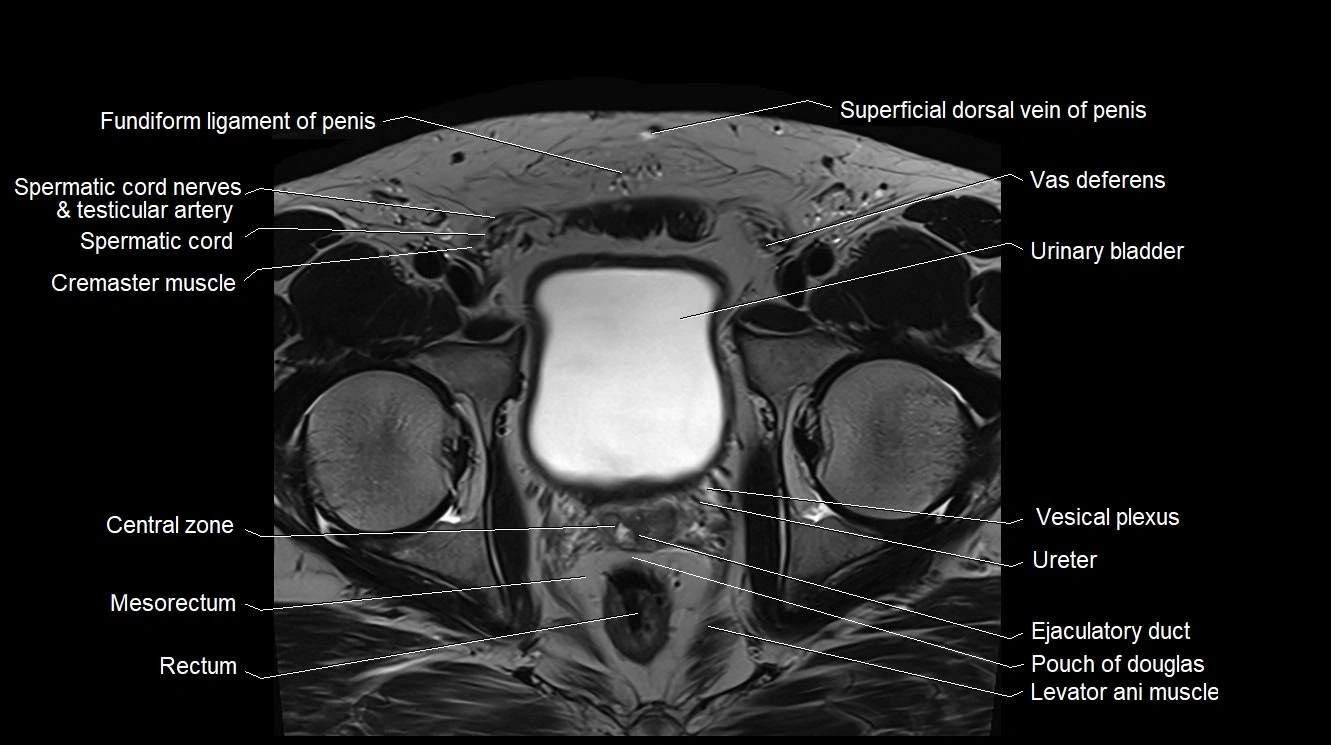

MRI image